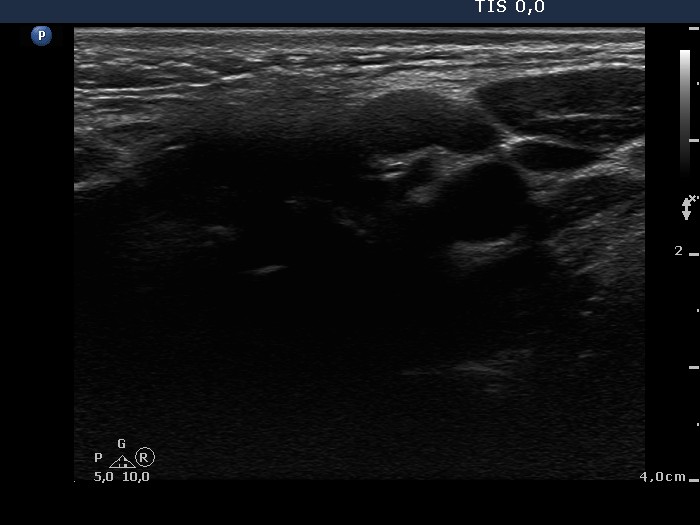

Lymph nodes - case conp 005 (ultrasonographic picture 7)

Left side of the neck, above the thyroid, longitudinal scan. The node lacks hilum.